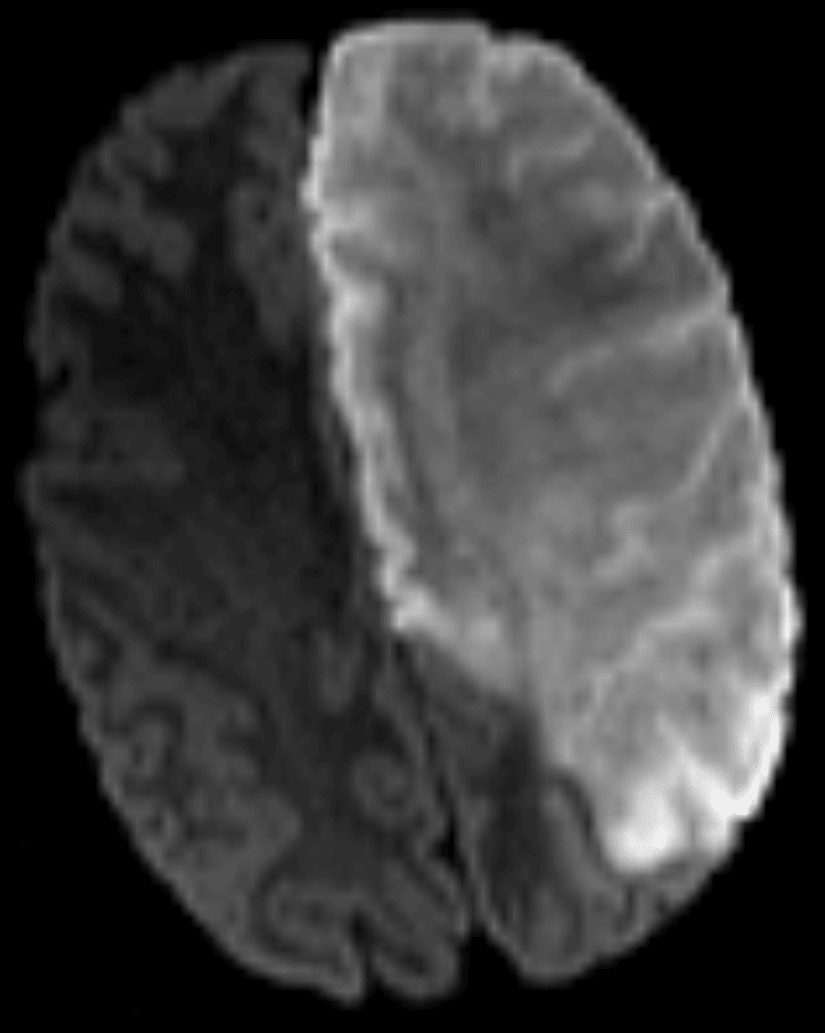

Representative diffusion-weighted MR image from this patient